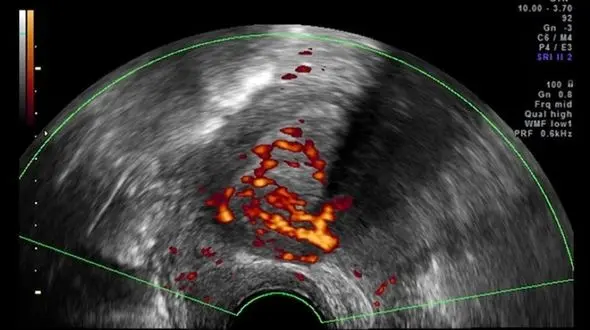

رکنا: رئیس کنگره بینالمللی چالشهای بالینی با اشاره به شیوع بیماری آندومتریوز در میان زنان، گفت: درمانهای دارویی ،لاپاراسکوپی و جراحیهای باز از جمله روشهای درمان این بیماری است.